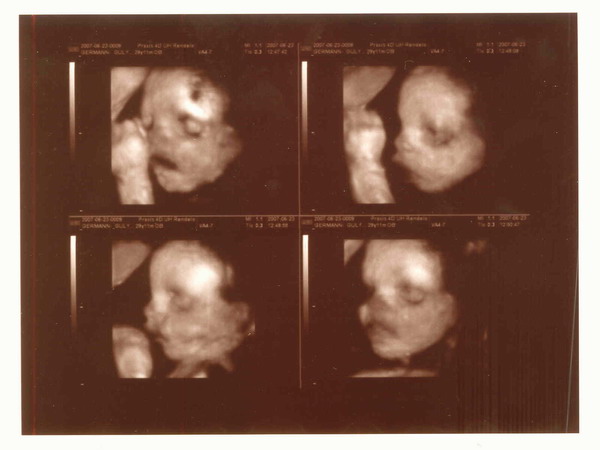

Nektarin, múlnak már a sebek a karodon? Szép kismama vagy, nagyon jók az uh. képek, nagy élmény volt így látni igaz? Én is élveztem anno. Jó pocakosodást, már nincs is sok hátra.